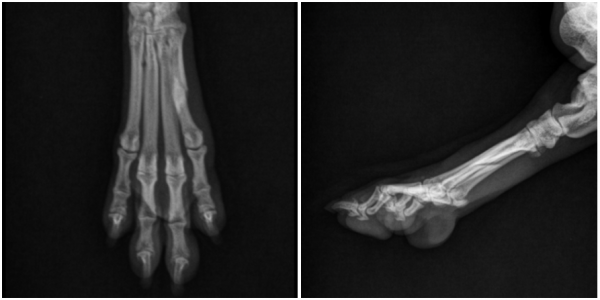

영상 검사(X-ray)를 통한 정밀 진단

정확한 병변 위치와 골절 형태를 확인하기 위해

방사선(X-ray) 검사를 시행하였습니다.

→ 영상 검사 결과

좌측 후지 5번째 발허리뼈에서

골절선이 명확히 확인되었으며, 골절 부위의 안정성이 떨어져

보존적 치료만으로는 회복이 어렵다고 판단하였습니다.